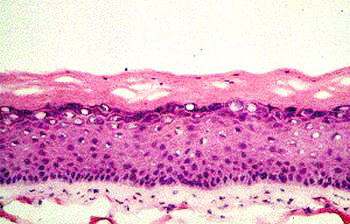

Aged skin can be recognized immediately by the presence of wrinkles, flaccidity and actinic keratosis. A histological section reveals some of the causes of these symptoms of ageing (Fig. 1 a and b).

Fig. 1a: Microscopic sections through the skin of a 21-year-old |

Fig. 1b: Microscopic sections through the skin of a 66-year-old |

Fig. 1

a and b

Microscopic sections through the skin of a 21-year-old and a 66-year-old

In young skin, the

lower part of the skin, the dermis, has a very regular structure. This

regularity is no longer so clear-cut in older skin. The dermis contains

irregular structures and flaws and appears less compact. The next highest

layer, the epidermis, is somewhat thinner in older skin than in younger.

More noticeable than this slight change in the thickness of the epidermis,

however, is the disappearance of the curvature of the epidermal-dermal

interface. In older skin this interface is flat, so that the cohesion

between dermis and epidermis is weaker. Finally, in the upper layer, the

stratum corneum, scarcely any differences can be observed under the microscope.

The main changes are therefore in the deeper layers of the skin, especially

the dermis. One of the biological causes is the major change in the collagen